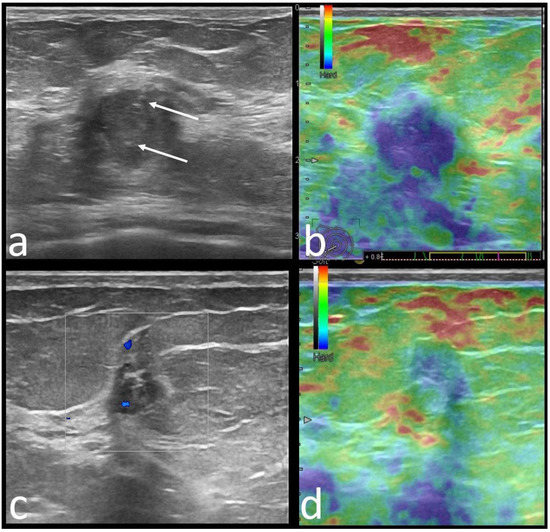

| Margins | |||

| Circumscribed | 22 (22.4) | 44 (30.3) | 0.226 |

| Non-circumscribed | |||

| Spiculated | 19 (19.4) | 46 (31.7) | 0.047 |

| Indistinct | |||

| Angular | 21 (21.4) | 19 (13.1) | 0.263 |

| Microlobulated | 10 (10.2) | 8 (5.5) | |

| Echo pattern | 0.000 | ||

| Hypoechoic | 57 (58.2) | 100 (70) | |

| Heterogeneous | 36 (36.7) | 19 (13) | |

| Isoechoic | 5 (5.1) | 26 (17) | |

| Posterior features | 0.000 | ||

| None | 39 (39.8) | 71 (49) | |

| Enhancement | 27 (27.6) | 12 (8.3) | |

| Strain Elastography | 0.029 | ||

| Soft | 40 (40), 9 BGR | 30 (20.6), 1 BGR | |

| US features (+/No. of patients) Orientation | NP (17/29) | NP (9/15) | NP (10/15) | P (7/15) | P (4/7) | P (4/6) | P (2/3) | P (2/3) |

| Margins | C (20/29) | NC (11/15) | NC (11/15) | NC (11/15) | C (5/7) | NC (5/6) | C (3/3) | NC (3/3) |

| Echo pattern | Hypoechoic (19/29) | Hypoechoic (9/15) | Heterogeneous (5/15) | Hypoechoic (11/15) | Hypoechoic (4/7) | Heterogenous (3/3) | - | Hypoechoic (2/3) |

| Posterior features | Enhancement (16/29) | Absent (9/15) | Shadowing (6/15) | Enhancement (6/15)/Combined pattern (5/15) | No posterior (4/7) | - | Enhancement (2/3) | - |

| Associated features | Hyperechoic rim (6/29) Soft elastography (11/29) | Calcifications (7/15) Hard elastography (12/15) | Calcifications (7/15) | - | - | Calcifications (3/6) Hyperechoic rim (3/6) | - | Calcifications (2/3) Architectural distortion (2/3) |